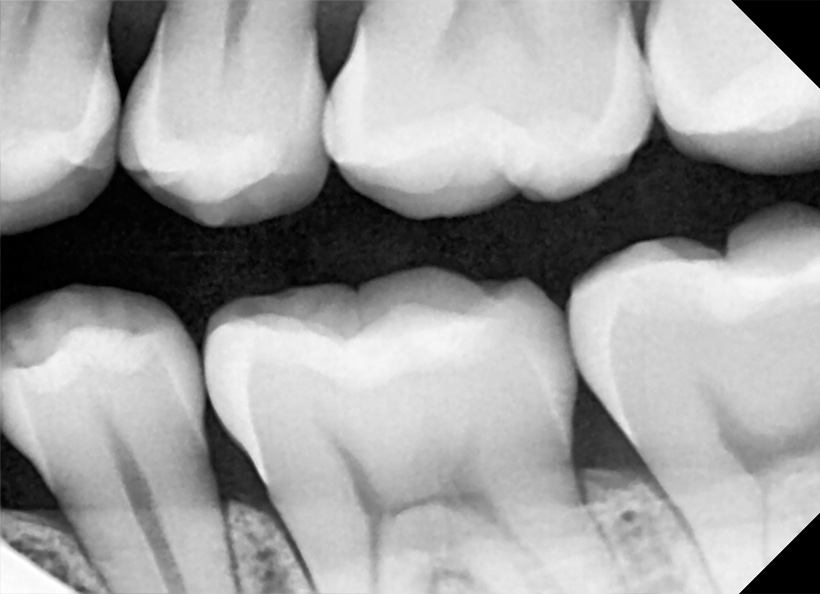

Radiografia digitală bitewing (muşcată) este o radiografie ce oferă informaţii precise (la fel ca şi radiografia retroalveolară) pe o zonă limitată a cavităţii bucale. Pe această radiografie medicul stomatolog poate vedea coroanele dinţilor, atât a dinţilor de pe maxilar, cât şi de pe mandibulă, cât şi rădăcina acestora. Este indicată în cazul cariilor interdentare, retracţiilor ososase, pungilor parodontale, etc.